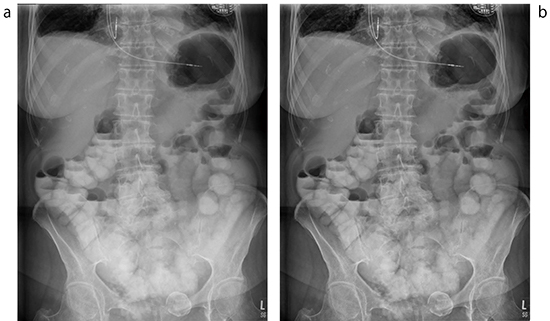

1.マルチ周波数処理の改善“UNIQUE2”

DigitalDiagnost C90は,従来のマルチ周波数処理を刷新し,鮮鋭度,ノイズ低減処理の改善などを施したUNIQUE2を搭載した。この改善された画像処理技術により,高水準の画像診断をめざす各施設のニーズに,より対応することが可能である。UNIQUE2は,アナトミカルプログラムと連動し,各撮影部位において自動で画像処理,調整が行われる。このため,撮影後すぐに適切な画像処理が施された画像が表示され,迅速なワークフローをも実現する。さらに,エキスパートモードとして,撮影後に画像処理パラメータを細部まで調整することができるため,より画質を追究することも可能である(図3)。

図3 従来のマルチ周波数処理(a)と新たな処理UNIQUE2(b)

特にUNIQUE2は骨盤腔内のコントラストが明瞭である。